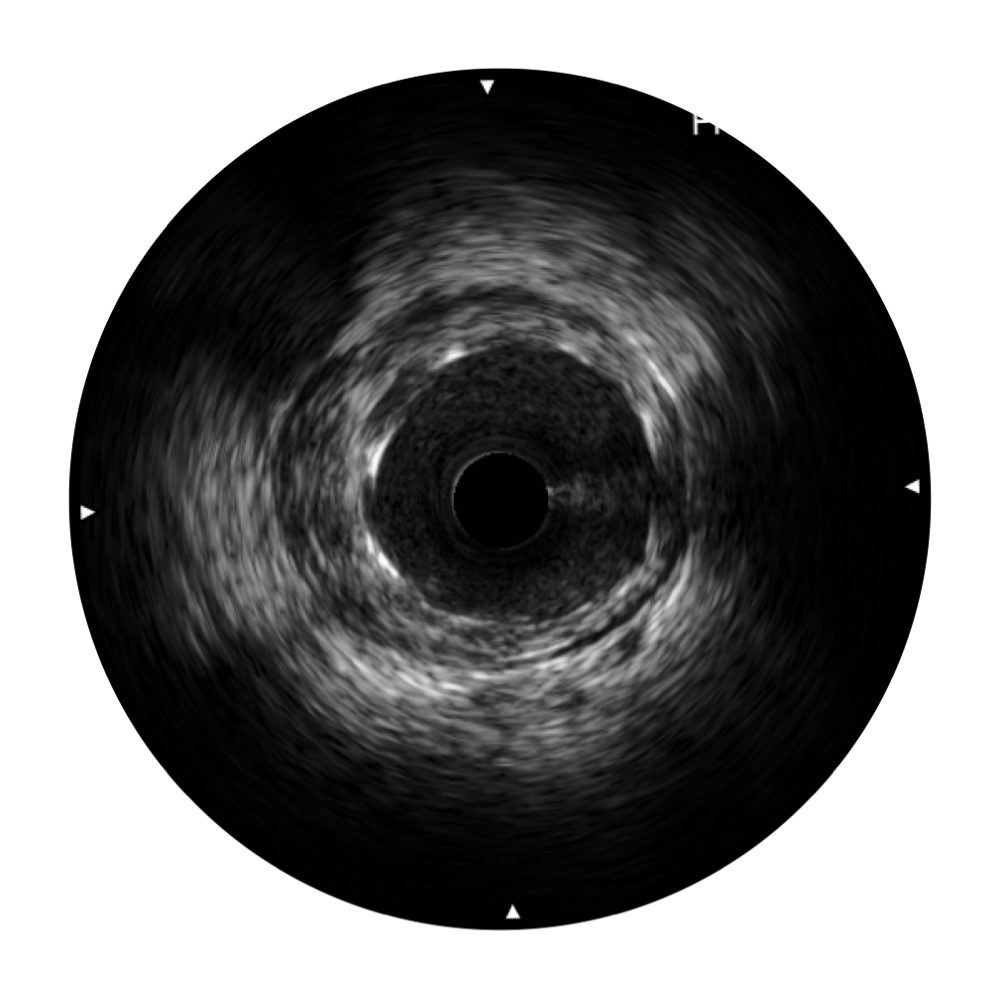

傳統(tǒng)IVUS圖像

對比傳統(tǒng)IVUS導管成像,開立寬頻IVUS圖像的近場支架梁顯影更細膩,遠場中膜外血管仍清晰可辨,兼顧遠中近,兼顧分辨力與穿透深度